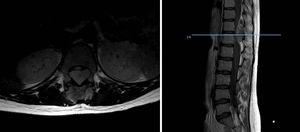

Con respecto a la supervivencia según localización axial/no axial, distinguimos 13 casos axiales y 28 no axiales. Dentro de los casos axiales, calculamos una tasa de supervivencia del 38,46% a partir del quinto año de seguimiento, del 30,77% entre los años primero y quinto y del 30,77% en los primeros doce meses de seguimiento. En el subgrupo no axial, la mortalidad durante el primer año asciende al 14,29%, un 46,43% sobreviven entre el primer y el quinto año, y un 39,29% siguen vivos al quinto año. Realizamos un subanálisis de los casos axiales diferenciando los casos pélvicos (8 casos, 61,54%) de los extrapélvicos (5 casos, 38,46%), y descubrimos que todos los pacientes con enfermedad pélvica fallecieron antes del final del seguimiento, la mitad de ellos durante el primer año y la otra mitad antes del 2.° año. Todos los casos axiales extrapélvicos, en los que encontramos un tumor epidural, un tumor paravertebral y tres tumores óseos en cuerpos vertebrales de D11, L2 y L3, sobrevivieron al final del seguimiento.

DiscusiónHemos analizado numerosos factores relacionados con el sarcoma de Ewing en una serie de 41 pacientes tratados en un mismo hospital en España durante 6 años. En nuestra serie, 2 tercios de los pacientes fueron varones y un tercio mujeres, siendo casi el 70% menores de 20 años de edad en el momento del diagnóstico anatomopatológico del tumor, datos que corresponden a lo descrito en la literatura1,4,7,8. Raramente se diagnostica en menores de 5 y en mayores de 303,13, en nuestra serie encontramos cinco casos (12,2%) en ese rango de edad: un paciente de 51 años y otro de 49 años de edad con formas extraesqueléticas (muslo –figura 3– y pierna respectivamente) y otros tres pacientes de 31, 32 y 35 años de edad con Ewing óseos en tibia y fémures respectivamente (fig. 4).

La localización pélvica del tumor constituye un factor de mal pronóstico para muchos autores, como para Bacci et al.18 quienes describen en su artículo de 2003 acerca de los Ewing pélvicos no metastásicos que los pacientes afectos de enfermedad pélvica poseen peor pronóstico que aquellos casos extrapélvicos. Plantean que esto pueda ser debido a que la localización pélvica del tumor dificulta el tratamiento local lo cual conlleva altas tasas de recidiva. En nuestro estudio contamos con 13 tumores axiales, 8 de los cuales fueron pélvicos. El 100% de los Ewing pélvicos fallecieron antes del final del seguimiento, la mitad de ellos durante el primer año y la otra mitad entre el primero y el quinto, no llegando la supervivencia en ningún caso a superar los 24 meses. Los casos axiales extrapélvicos presentaron una supervivencia del 100% a partir del quinto año de seguimiento.